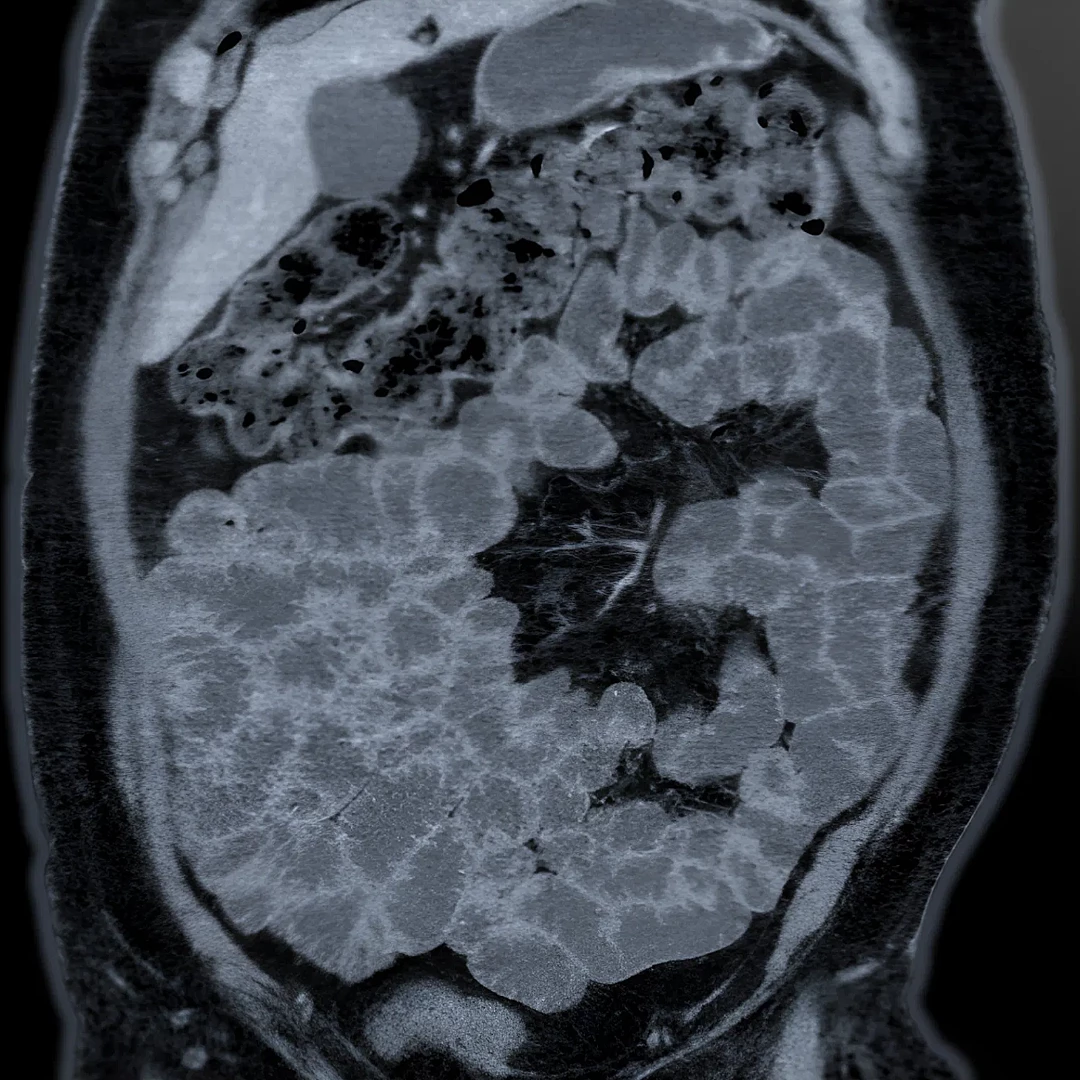

CT Enterography is a specialized scan that captures detailed images of the small intestine to detect inflammation, tumors, or Crohn’s disease. It combines oral contrast and low-dose CT to provide clear, non-invasive evaluation of bowel conditions.

Virtual Colonoscopy CT uses advanced imaging to create a 3D view of the colon, detecting polyps or tumors without traditional colonoscopy. It’s a quick, non-invasive screening option for colorectal cancer.